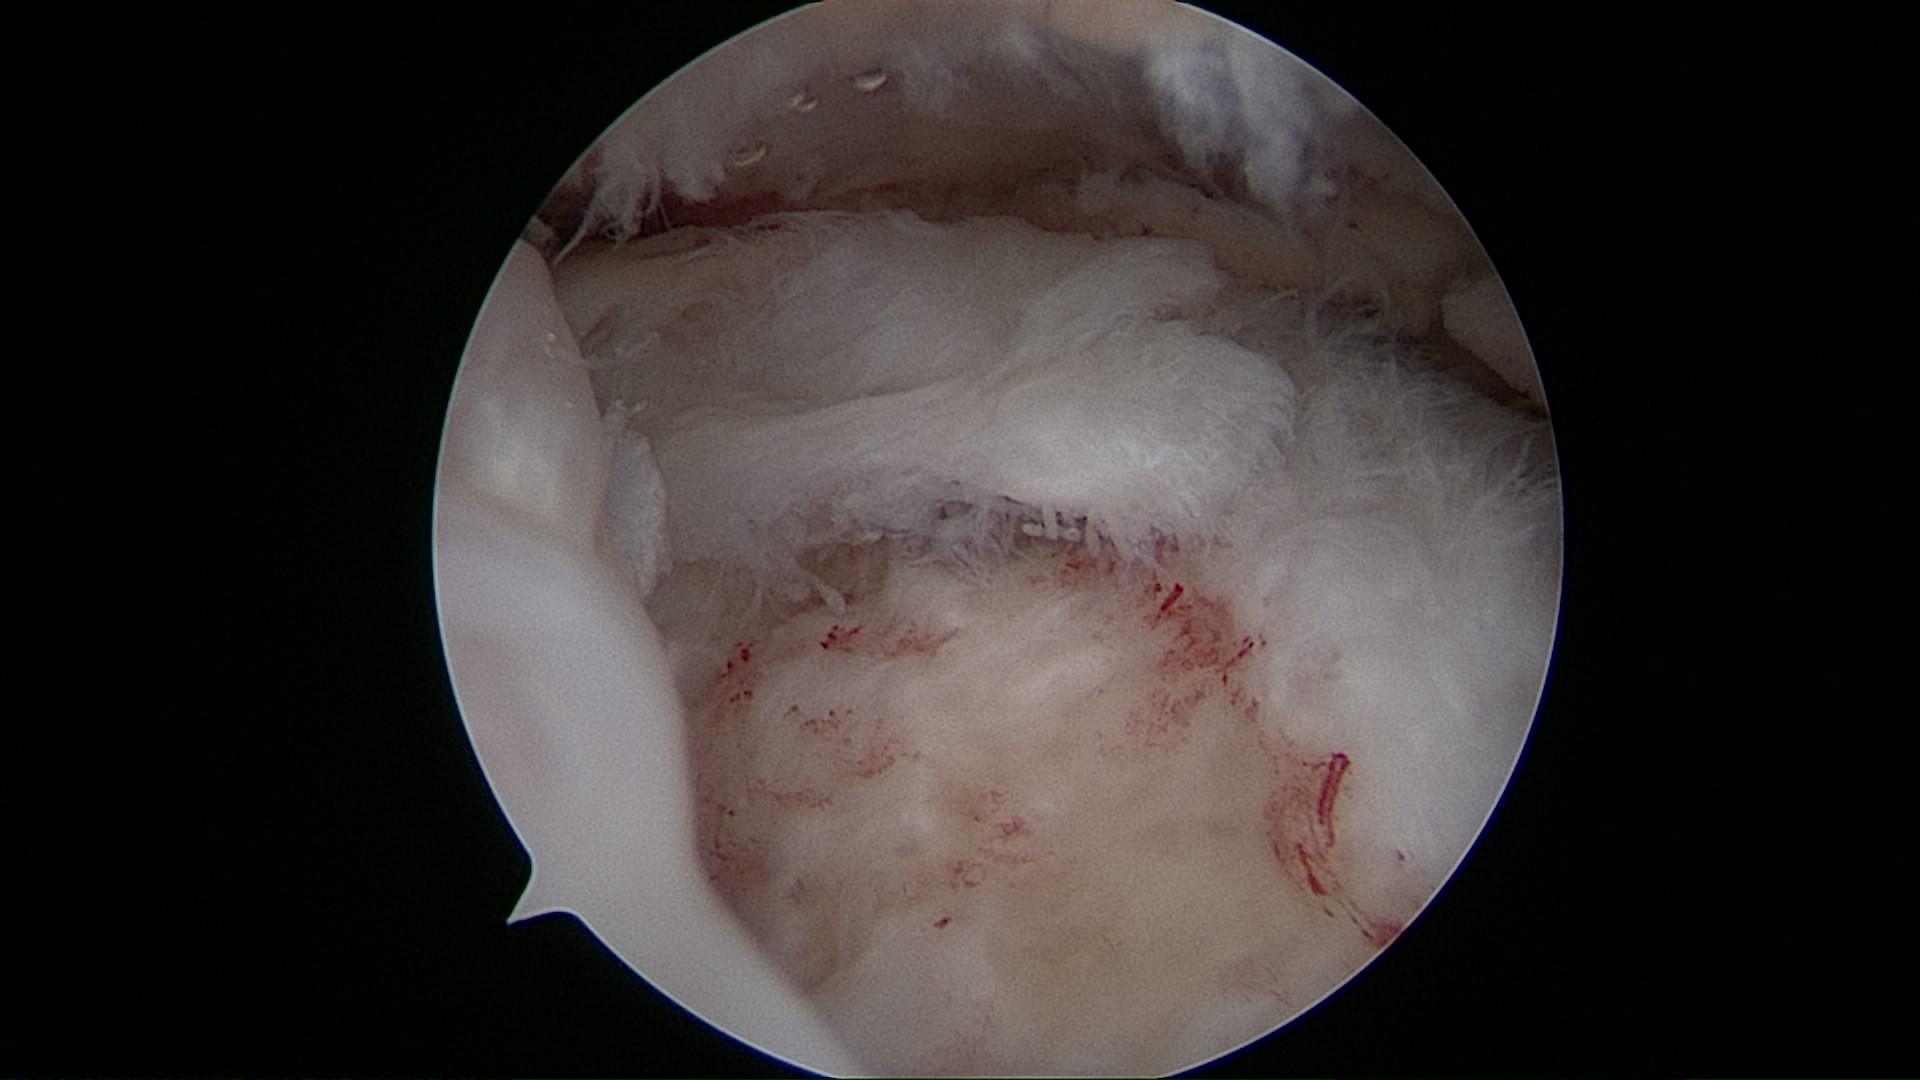

Lesión de Manguito Rotador

Reparación de Manguito Rotador con suturas y anclaje

Cirugía de reparación de manguito rotador con suturas y anclajes

Cirugía manguito rotador con suturas y anclajes